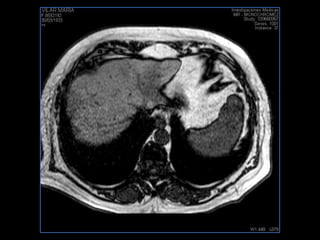

PROTOCOLO hígado graso AXIAL in phase y out phase AX T1 y AX fat sat +SAG T2  CON   GADOLINIO :  COR T1+AX T1(DIN) SAT: NO  FASE: RL THK: 4MM  COIL:  GAP: (FACTOR 1.4)  FOV: 40 CM NEX:2 SINCRONIZACION RESPIRATORIA EN 3 O 4 CICLOS ALE

PROTOCOLO hemocromatosis AXIAL supresión grasa /AX multieco en higado COR T2 AX T1 +SAG T2  CON   GADOLINIO :  COR T1+AX T1 SAT: NO  FASE: RL THK: 4MM  COIL:  GAP: (FACTOR 1.4) 1MM FOV: 40 CM NEX:2 SINCRONIZACION RESPIRATORIA EN 3 O 4 CICLOS ALE

resonancia de abdomen